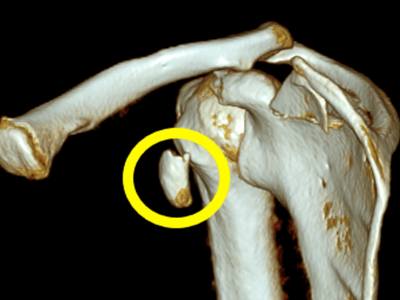

Overview: Coracoid fractures are rare injuries often associated with other shoulder injuries like AC joint dislocations or fractures of the scapula, clavicle, and humerus. What is the Coracoid Process? The coracoid process is a small bony projection on the scapula…